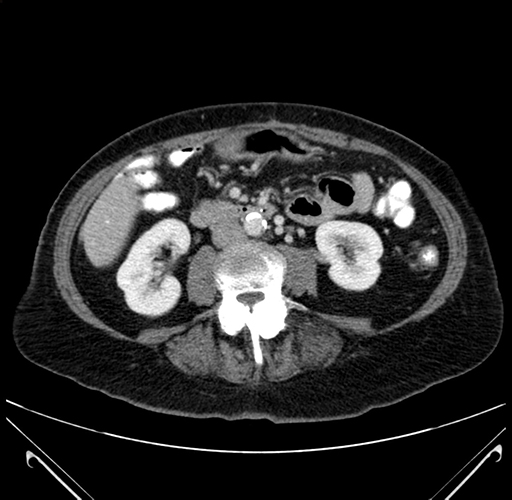

Axial Venous